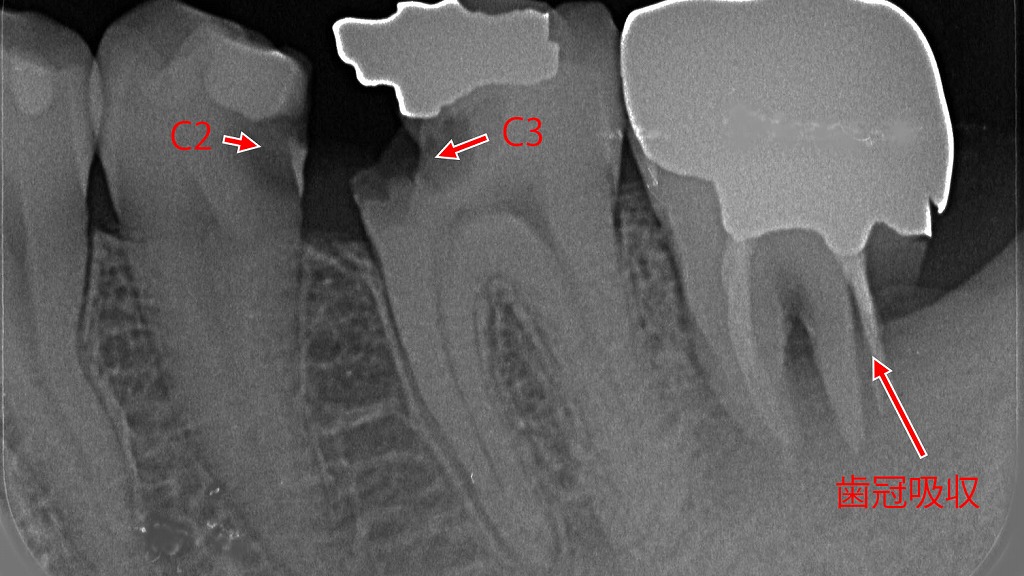

下顎4・5・6番の重度虫歯による歯髄炎

この写真は 下顎の4番・5番・6番の歯(小臼歯〜大臼歯)に深い虫歯が進行し、歯髄炎(歯の神経の炎症)を起こしている状態です。

- 初期虫歯(C0〜C1)は痛みがありませんが、象牙質(C2)に進行すると冷たいものがしみ、

さらに歯髄(C3)に達するとズキズキする激痛が発生します。